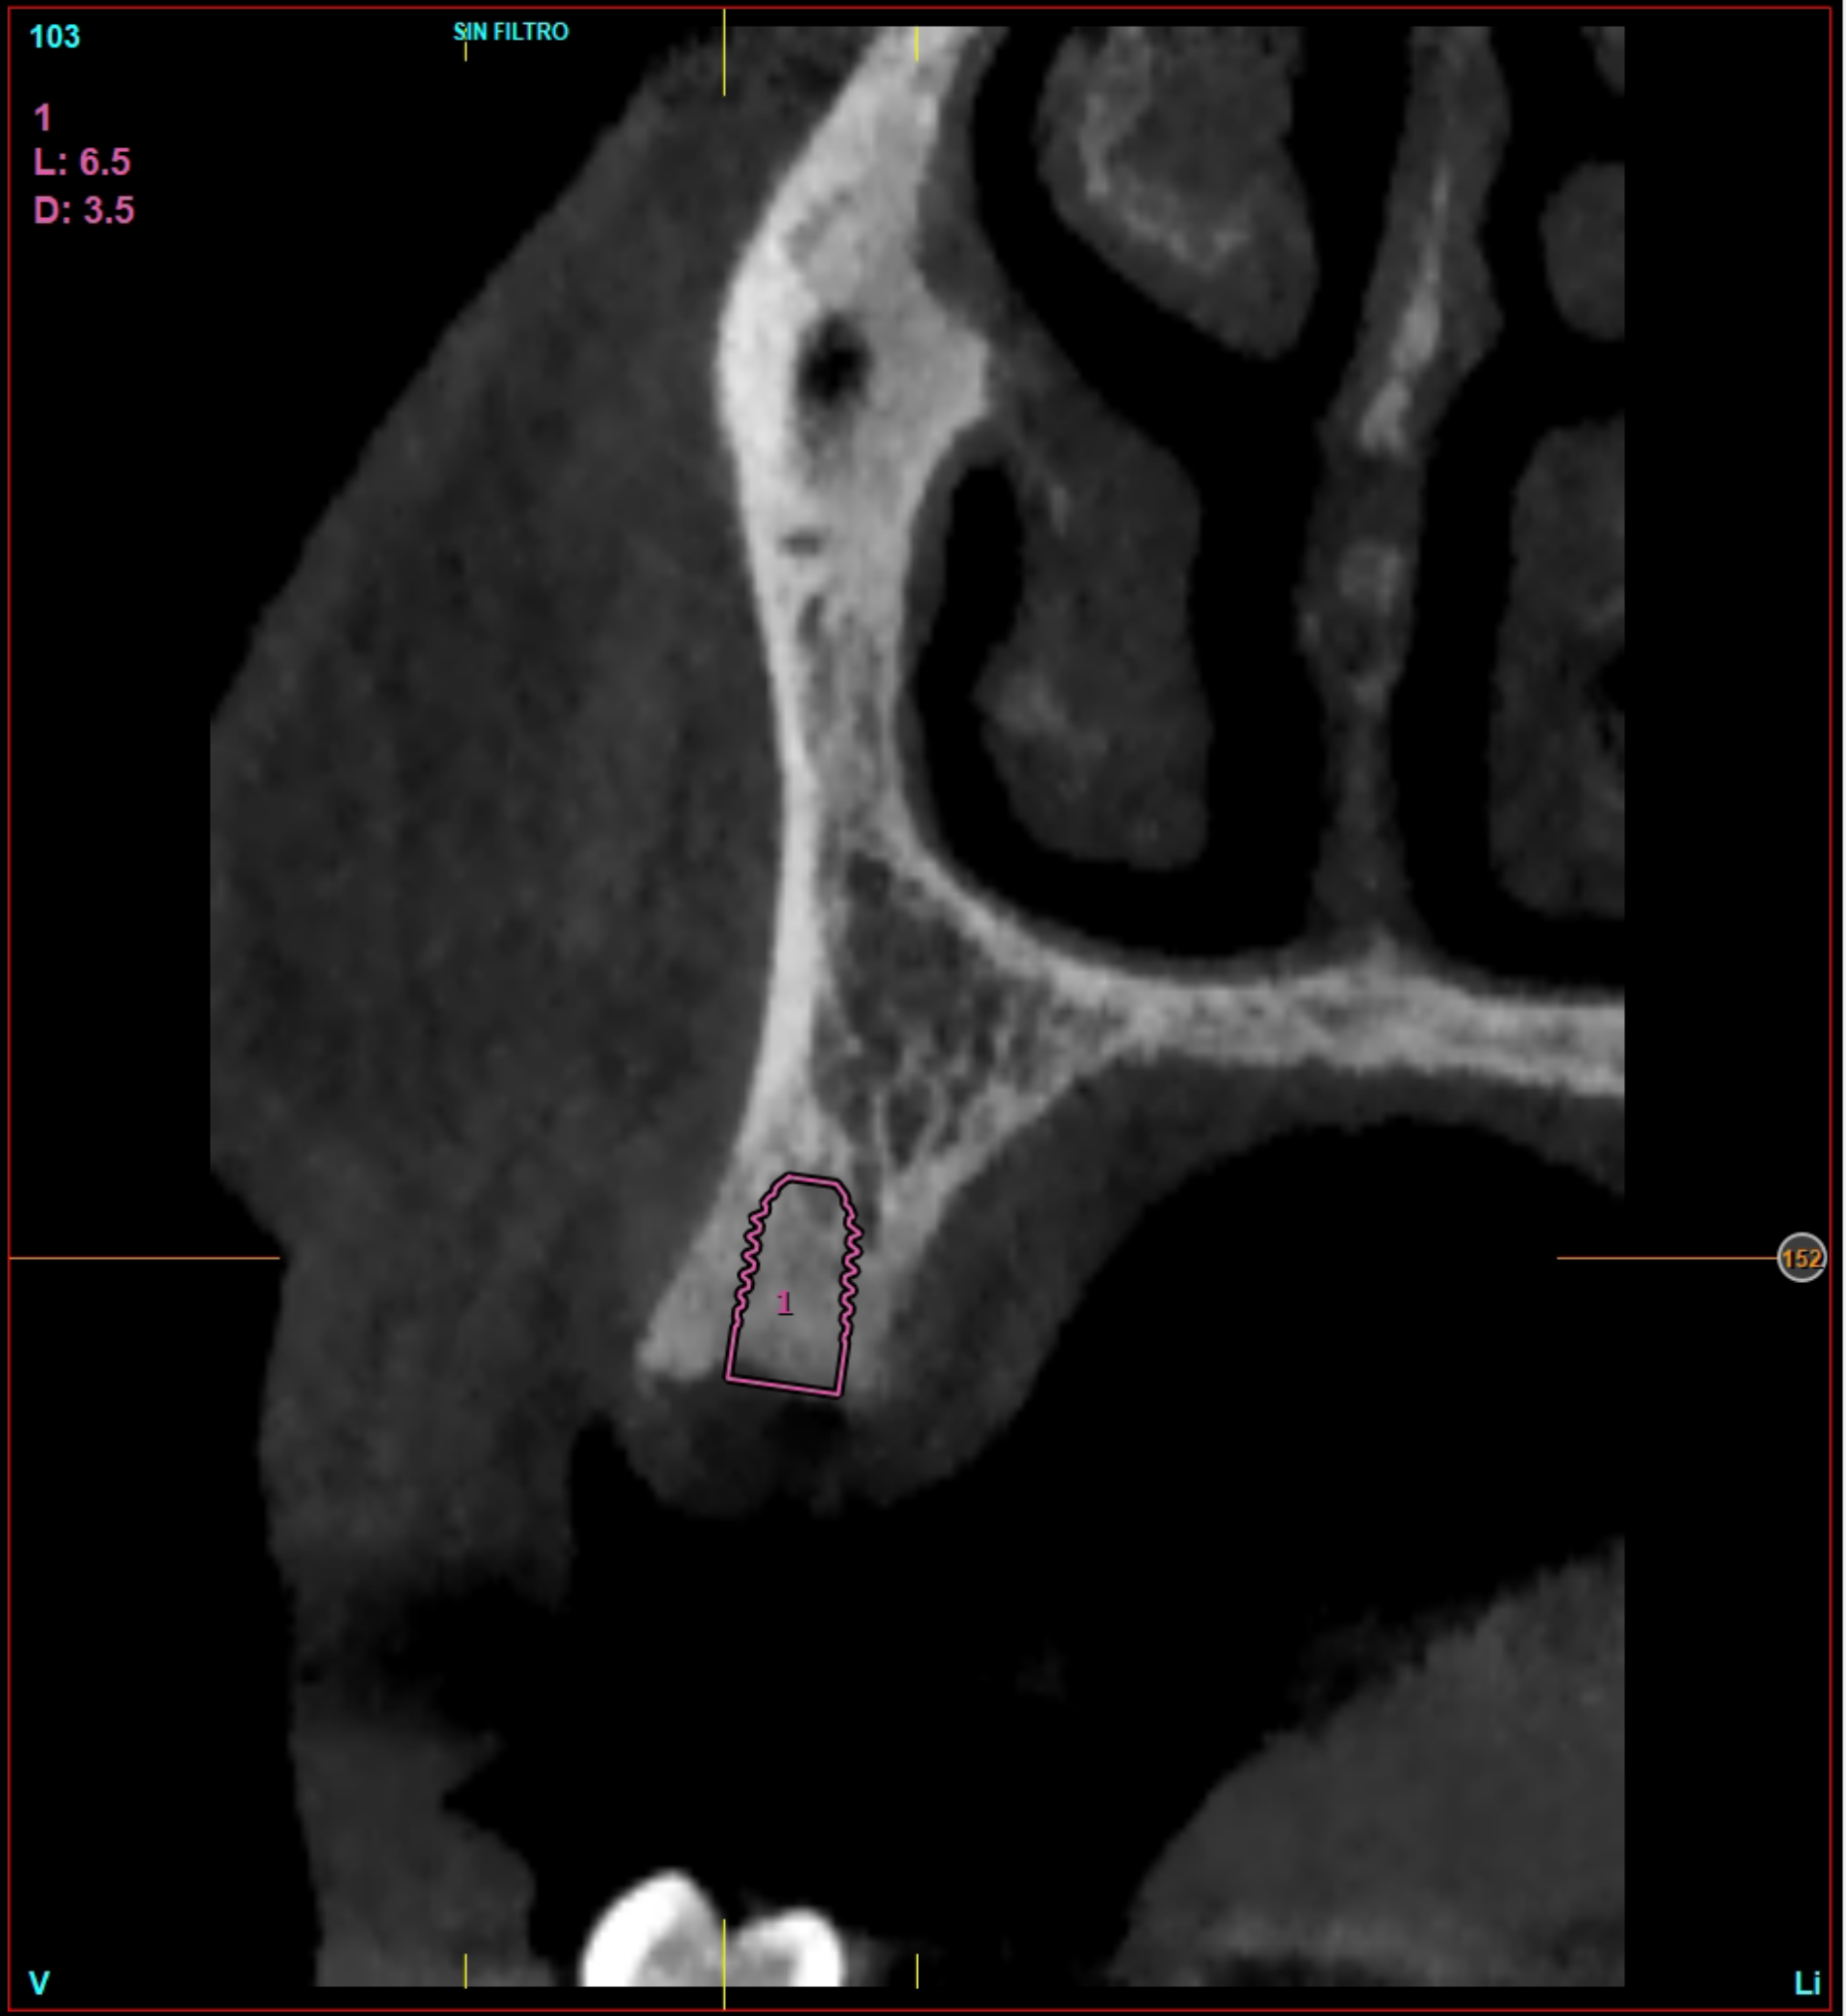

La pianificazione preoperatoria virtuale ha incluso la scansione intraorale e la CBCT. Con i dati raccolti sono stati generati modelli virtuali altamente precisi dell’anatomia del paziente ed è stata pianificata la posizione ideale degli impianti. In base a questa pianificazione sono state prodotte dime chirurgiche CAD/CAM per replicare la posizione e l’angolazione implantare pianificate. Le dime sono state fatte calzare sui denti adiacenti, incorporando i driver statici coerenti con il manipolo chirurgico utilizzato dall’operatore (Figura 1).

Grazie a dima e drivers, la chirurgia guidata consente una fresatura biologicamente incrementale come con un protocollo convenzionale; l’osso autologo raccolto durante la fresatura può essere utilizzato come particolato da innesto al bisogno. I dati clinici e demografici raccolti includono età, sesso, storia clinica e terapie farmacologiche in atto. I dati correlati agli impianti includono, invece, localizzazione anatomica, diametro, lunghezza, torque di inserzione, tipo di protesi, e parametri ossei rilevati alla diagnosi (Figure 2-3). Nel corso del follow-up sono stati registrati la sopravvivenza implantare protesica e il livello di osso marginale. I dati sono stati registrati da un esaminatore indipendente.

Il 20% degli impianti è stato posizionato nella mandibola (per lo più in posizione 47) e il restante 80% nel mascellare superiore (il 20% in posizione 16 e il 20% in posizione 25). Gli impianti posizionati nel mascellare superiore hanno trovato un osso tipo IV, mentre gli impianti posizionati nella mandibola hanno trovato un osso tipo III. Gli impianti utilizzati hanno un diametro compreso tra 4.0 e 4,5 mm (il 66.7% sono da 4.0 mm) e una lunghezza compresa tra 4.5 mm e 7.5 mm (il 53.3% sono lunghi 7.5 mm). Nell’86.7% dei casi non è stato eseguito alcun procedimento chirurgico aggiuntivo; in un caso, due impianti hanno previsto in rialzo di seno transcrestale con PRGF-Endoret e osso autologo. Nel 93.3% dei casi la protesizzazione ha previsto ponti avvitati a più elementi; un impianto è stato protesizzato mediante elemento singolo avvitato con componente transepiteliale. Il follow-up medio è stato di 12.4 ± 1.05 mesi dal carico. Il 100% degli impianti è sopravvissuto, senza complicanze né chirurgiche né protesiche. La perdita di osso media a 12 mesi è stata mesialmente di 0.15 ± 0.74 mm e distalmente di 0.13 ± 0.85 mm. La Figura 4 mostra l’osso perso su un singolo impianto e le Figure 5-14 illustrano un caso clinico rappresentativo.